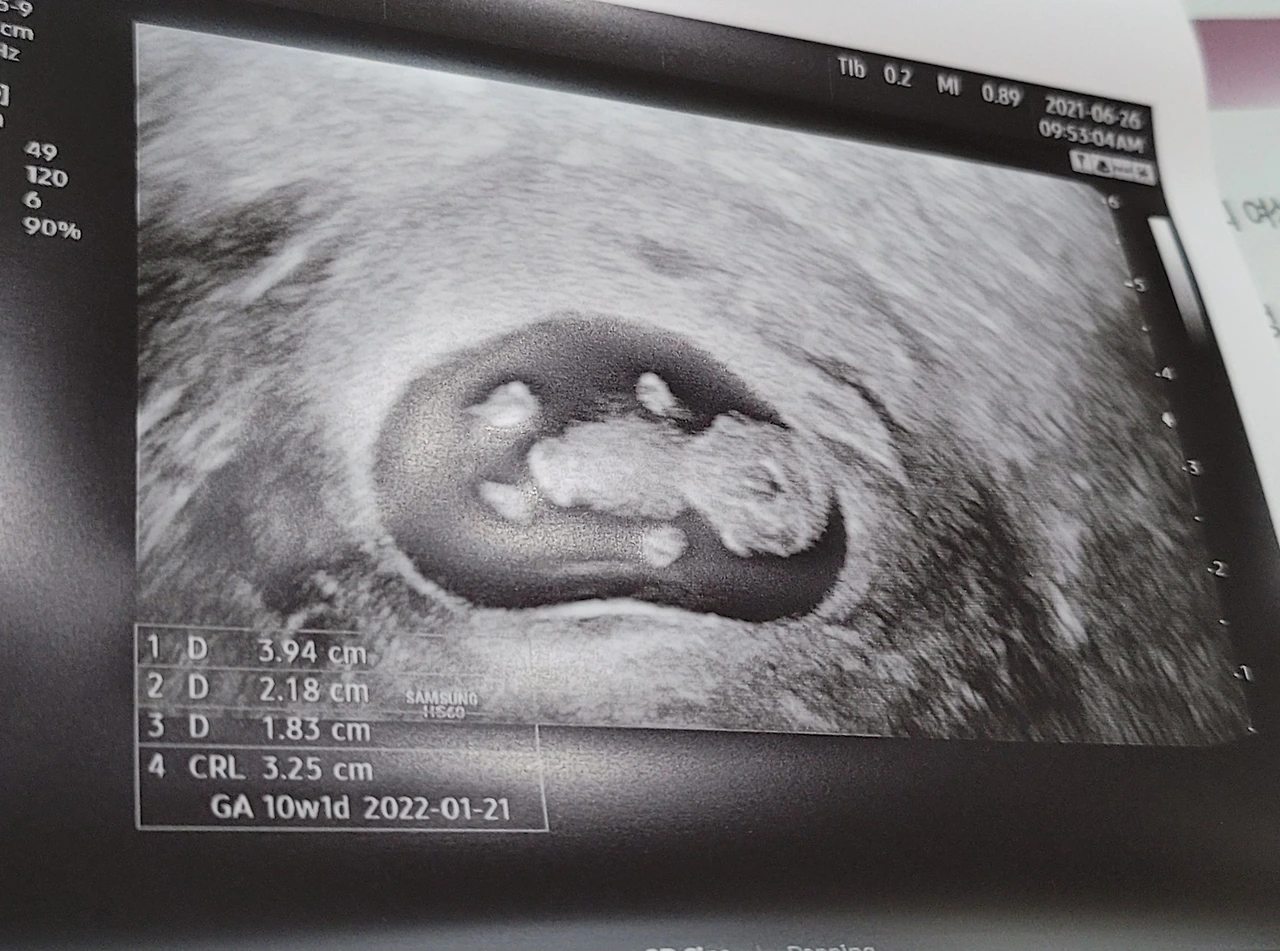

항암제를 달고 오신 장모님은 우리가 건넨 사진을 받아 들었다.

젤리곰 형태, 머리와 팔 다리가 보인다.

"임신했어, 이제 안정기라 말하는 거야. 조그만 게 사람이래"